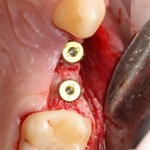

Например, в следующей ситуации:

Оставить так, как есть — это значит, сильно рисковать имплантом и объемом альвеолярного гребня — фактически, большая часть импланта пятого зуба «висит в воздухе». Поэтому получившуюся костную полость мы заполняем аутокостной стружкой в смеси с Bioss и закрываем коллагеновой мембраной BioGide:

При необходимости, мембрану можно фиксировать пинами.

Через три месяца результат:

можно ставить формирователи и заканчивать лечение:

В указанном выше случае использование костных блоков просто невозможно.